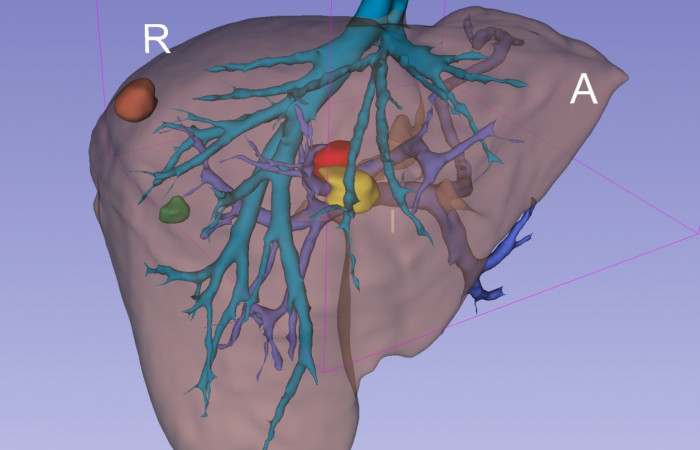

Pracownia Funkcjonalnego i Wirtualnego Medycznego Obrazowania 3D (Pracownia 3D-FM) funkcjonuje w strukturze Zakładu Diagnostyki Obrazowej Szpitala Uniwersyteckiego w Krakowie pod kierownictwem Prof. dr hab. Tadeusza Popieli. Jej celem jest opracowanie i wdrożenie innowacyjnych metod przetwarzania oraz analizy sygnałów i obrazów medycznych, w tym wykorzystanie technologii rzeczywistości wirtualnej oraz metod obrazowania funkcjonalnego. Rozwiązania te wspierają przedoperacyjne planowanie, monitorowanie procedur medycznych oraz wzbogacają proces diagnostyczny o nowe formy wizualizacji danych medycznych.

Pracownia 3D-FM zajmuje się m.in. następującymi obszarami:

- Tworzeniem modeli 3D do celów przedoperacyjnego planowania oraz wizualizacji diagnostycznej.

- Rozwojem rozwiązań programowych do obrazowania medycznego.

- Obrazowanie Medyczne 3D

- Segmentacja i analiza danych DICOM

- Rekonstrukcja danych medycznych

- Technologie immersyjne (mieszana, rozszerzona i wirtualna rzeczywistość)

Pracownia Funkcjonalnego i Wirtualnego Medycznego Obrazowania 3D łączy nowoczesne technologie z praktycznym zastosowaniem w diagnostyce i terapii. Dzięki interdyscyplinarnej współpracy oraz zaawansowanym narzędziom badawczym dążymy do podnoszenia standardów opieki medycznej w Szpitalu Uniwersyteckim w Krakowie.